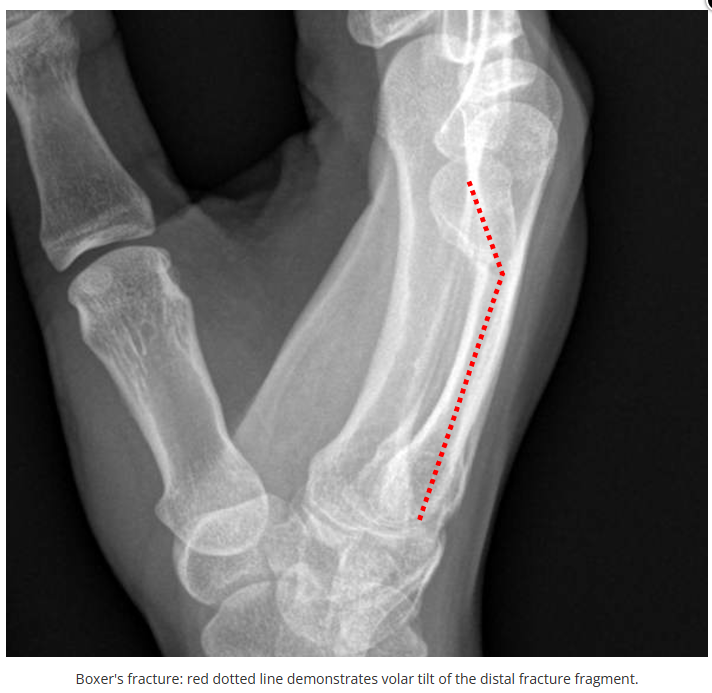

今天是腕部与手的X线片。所有X线片都

带有标注和说明

,可以选择长按图片,

自动翻译相关说明